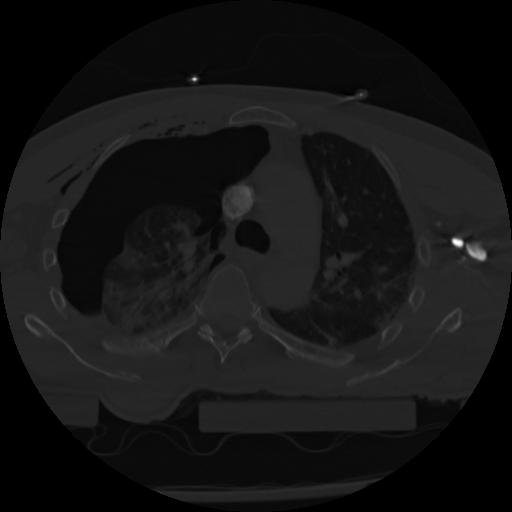

22 ANGIO,CE,Vol,0.5,ANGIO,,